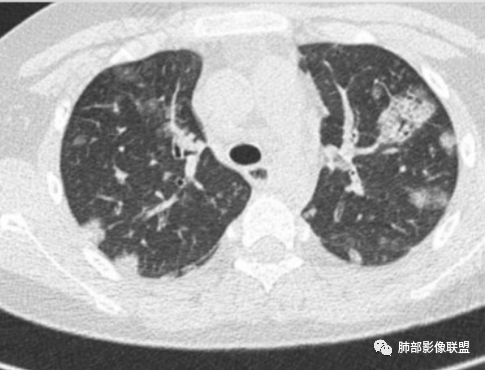

少年患者,游泳后发热畏寒,呼吸困难,两肺弥漫分布结节及磨玻璃影,考虑寄生虫感染,钩体病?

外伤后与河水接触史,病灶分布随机,点晕征,淋巴低,CRP、降钙素高。休克血压。考虑感染性病变:钩端螺旋体病

两肺散在磨玻璃影,靠近胸膜多见,边缘有晕征,考虑感染性疾病,真菌感染

青少年,双肺多发结节斑片影,肝密度减低,有下水的经历,PCT太高,考虑感染性疾病,钩体病?金葡菌脓毒性栓子?

患者河里游泳,受伤,发热,血压低到休克,呼吸困难三凹征,血气提示呼吸性碱中毒合并代谢性酸中毒且代酸占上峰,肺部表现既无明显出血的磨玻璃影(不符合钩体导致出血的特征)又无多发影内空洞(这点不符合金葡菌),是真菌感染的影像,河水属污水,故肺部表现为:尖端赛多孢子肺炎(这个菌感染重,死亡率高)!

青少年,河水不知道是否污染,气道分布斑片影,pct,crp高,g-杆菌,周围似见晕征,脓毒性肺栓塞,金葡,钩体感染

男14岁,2天前下河游泳史,发热;两肺近外带可见磨玻璃密度影,边缘疑似晕征,结合实验室检查,符合感染,倾向真菌感染,支持肺钩端螺旋体病。

宇宙:

青少年男性,2天游泳后发热,双肺多发斑片状,结节状阴影,多分布肺外带,血道来源,部分病灶边缘可见磨玻璃影,患者有明显脂肪肝病史,考虑.感染性病变,金黄色葡萄球菌?钩体?肺克?

青少年,河沟游泳后急性发病,左侧髋部疼痛,双肺弥漫地方结节、斑片模糊影,CRP、PCT明显增高,考虑钩体病,鉴别血播金葡

PCt>200,脓毒血症了,有无皮肤损伤?诱因游泳,高处跳水,与水有关,影像为多发毛玻璃结节,有细网格样改变,内可见支气管影,所以是间质改变➕肺泡渗出;结节分布是随机分布,血源性。与临床相对应。感染性病变,pct不支持病毒排除。细菌,金葡?军团?需复查看看病情转变。有无三红三痛,如有,钩也可能。寄生虫待排。

急性起病,游泳史,寒战发热,感染指标明显升高,胸部CT双肺多发磨玻璃影,实变,内可见支气管扩张,大致呈间质改变,随机分布,首先考虑感染性疾病。

青少年,多发斑片影,有游泳史,伴CRP及PCT升高,首先考虑血源性葡萄球菌感染

年轻患者,急性起病,高处跌下,皮肤损伤,两肺胸膜下多发实变,边缘见磨玻璃影,部分实变呈楔形,实变内见粗网格影,部分实变见反晕征,综和病史考虑感染性病变,影像上符合脓毒性肺栓塞,支持血源性金葡菌感染,鉴一下COP

青年人,有游泳史,畏寒发热,双肺内及胸膜下多发实变,边缘见磨玻璃密度影,部分呈反晕征,内可见多发网格样改变,考虑感染性病变,金葡菌感染

双肺叶结节及斑片状磨玻璃样密度,边缘清,外周分布为主,部分见供血血管,分布特点符合Spe表现,青少年,高处跳落游泳史,左侧盆部疼痛,畏寒发热,CRP和Pct显著升高,考虑血行感染,金葡?至于大家考虑的钩端螺旋体病和嗜水单胞菌不是太了解

青少年发病急,高热,双肺多发斑片状磨玻璃影,边界模糊,以胸膜下为主,考虑感染性病变,金葡菌可能

月亮圆了!:

青年,游泳,盆骨处疼痛”原因?”,畏寒,发热,Pct明显升高。双肺多发斑片,结节影。胸膜下也有。考虑血播。金葡可能大

游泳,高处跳下盆骨疼痛,肺上血播及气道均有,符合感染性病变,吸入性病变,金葡菌肺炎要考虑

流心明智:

男,14岁,高处跳下,游泳后畏寒。胸部CT:两肺多发斑片影、结节影;沿支气管血管束分布,胸膜下也有;密度以GGO为主,部分为mGGO;边缘部分清楚,大部分模糊;内可见网格影、支气管充气征。考虑:SPE?肺水肿?鉴别淋巴瘤。